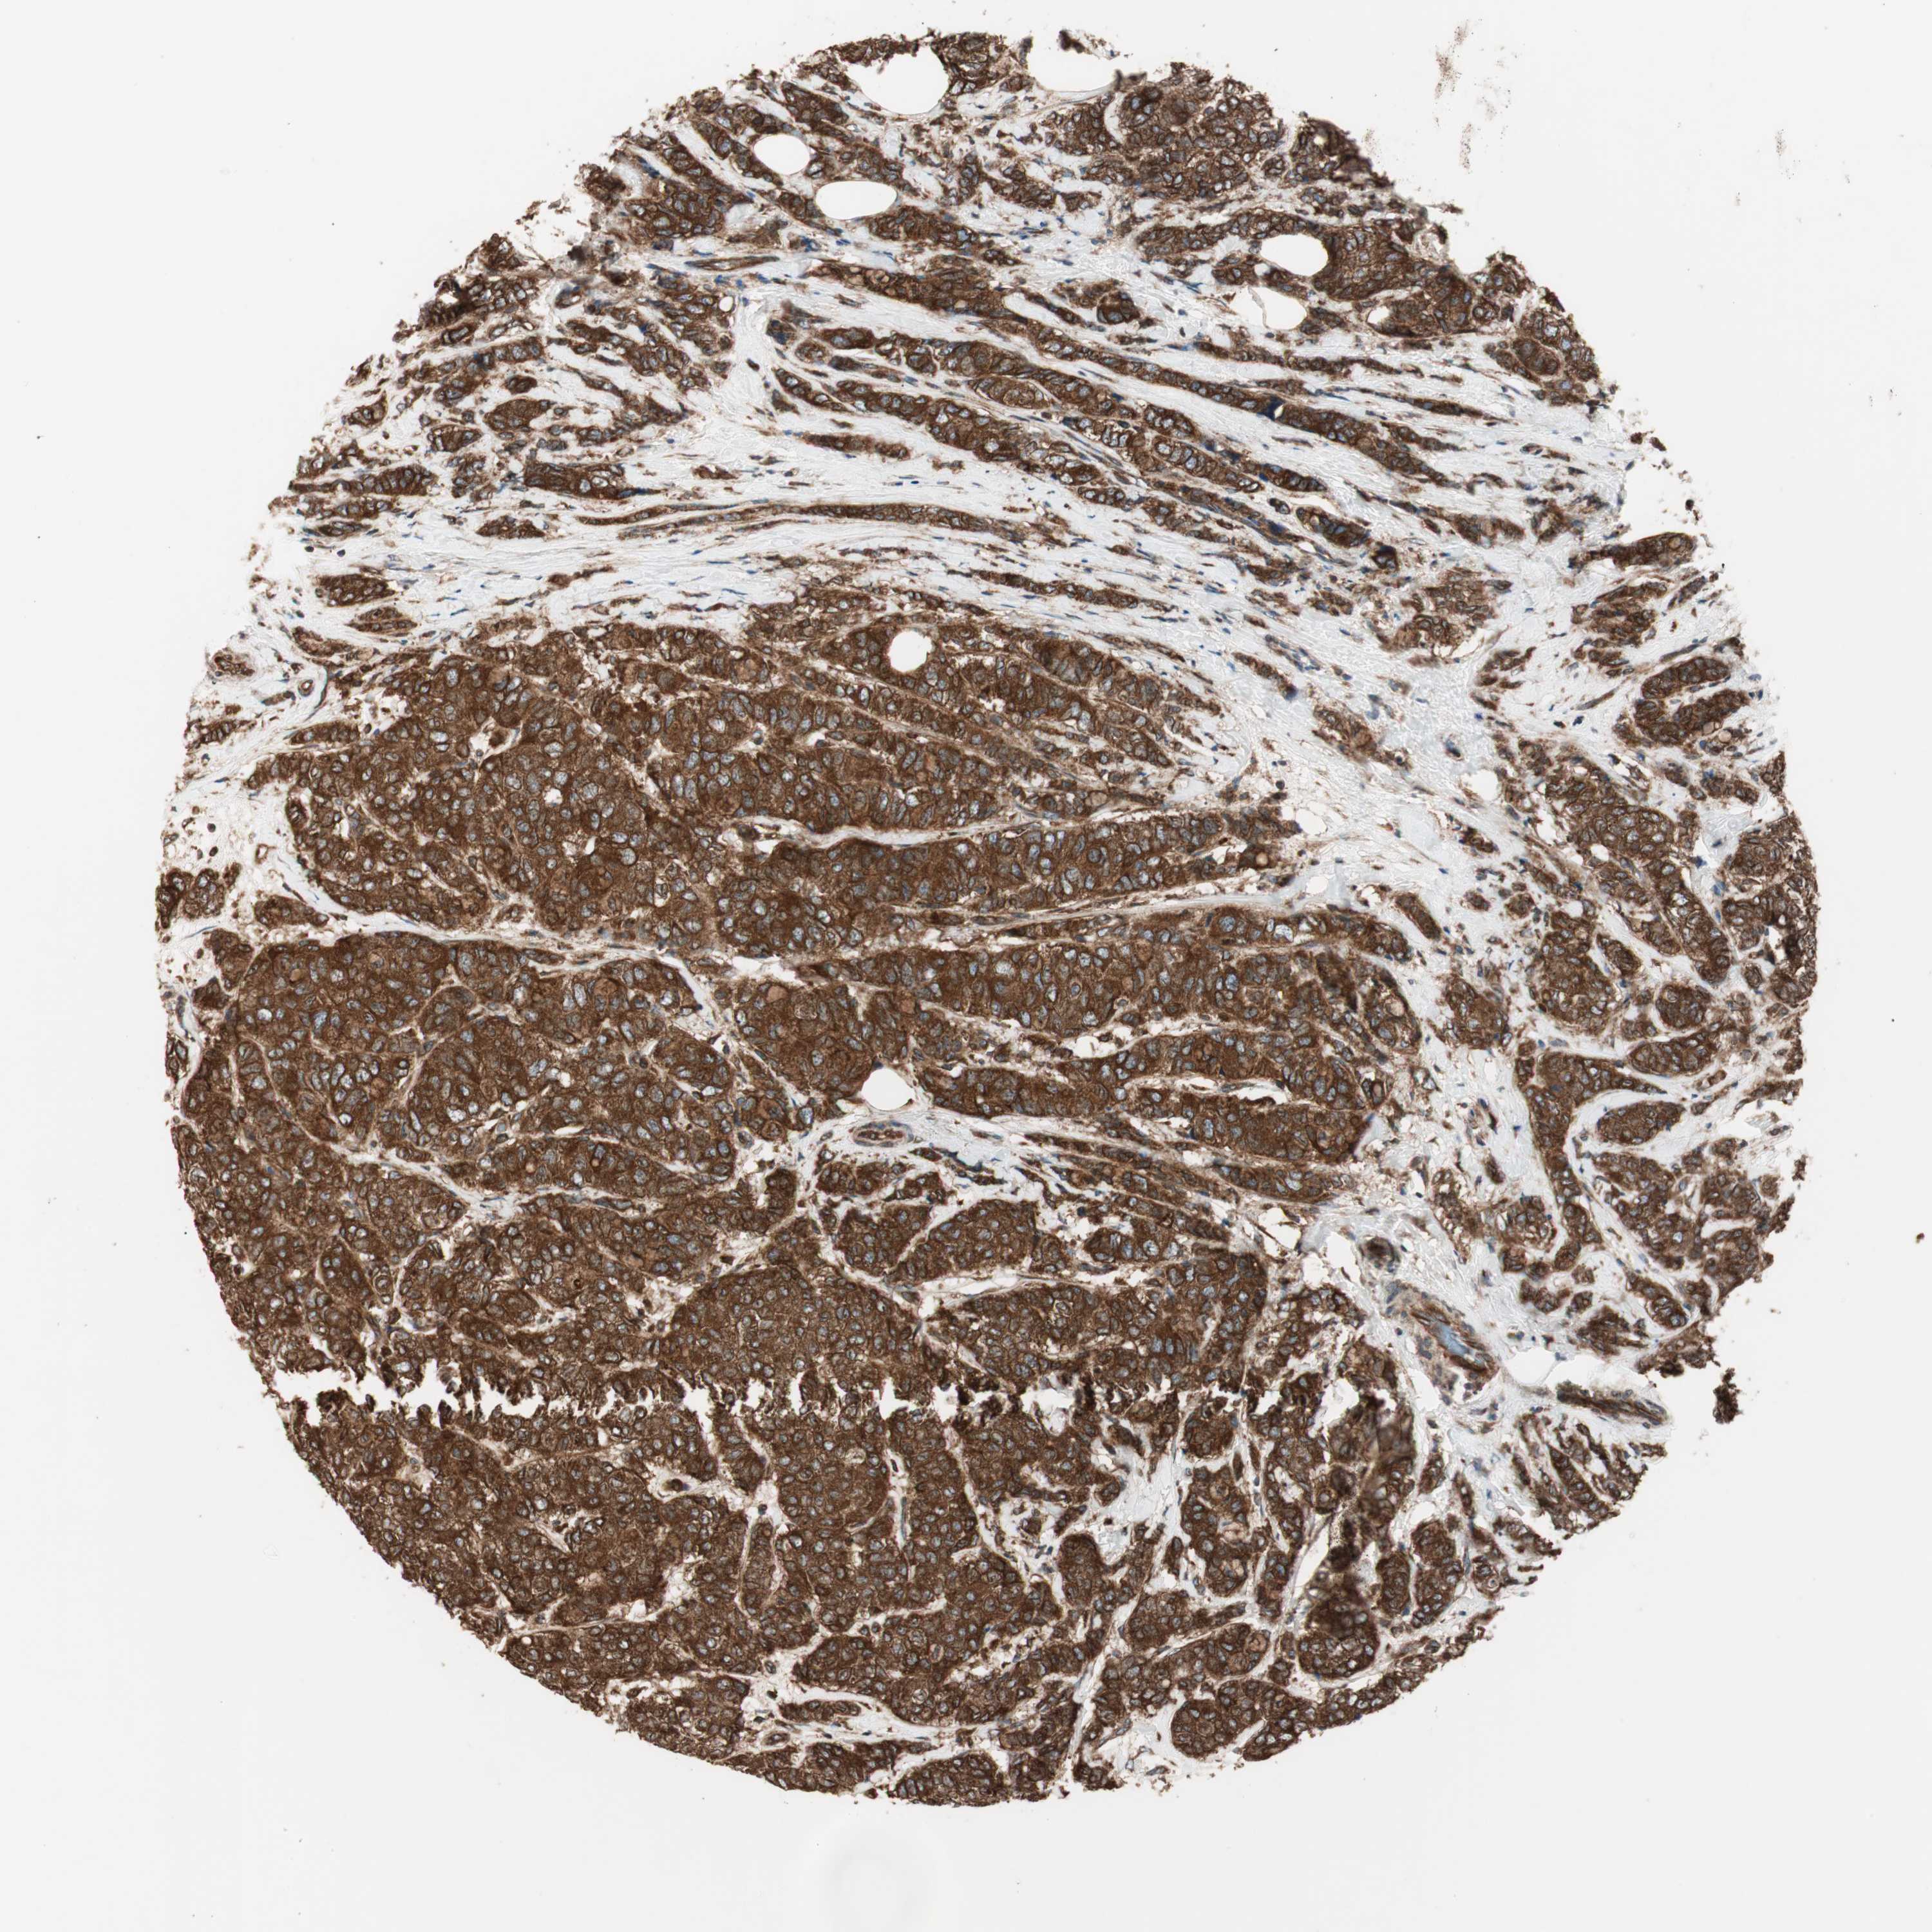

CANCER BREAST CANCER Show tissue menu

BRCA TCGA BRCA VALIDATION PROTEIN EXPRESSION